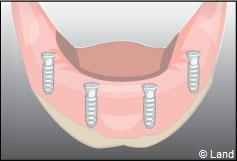

Exemple de 3 dents manquantes remplacées par 3 couronnes sur implants.

Pose des piliers prothétiques et des 3 couronnes scellées.